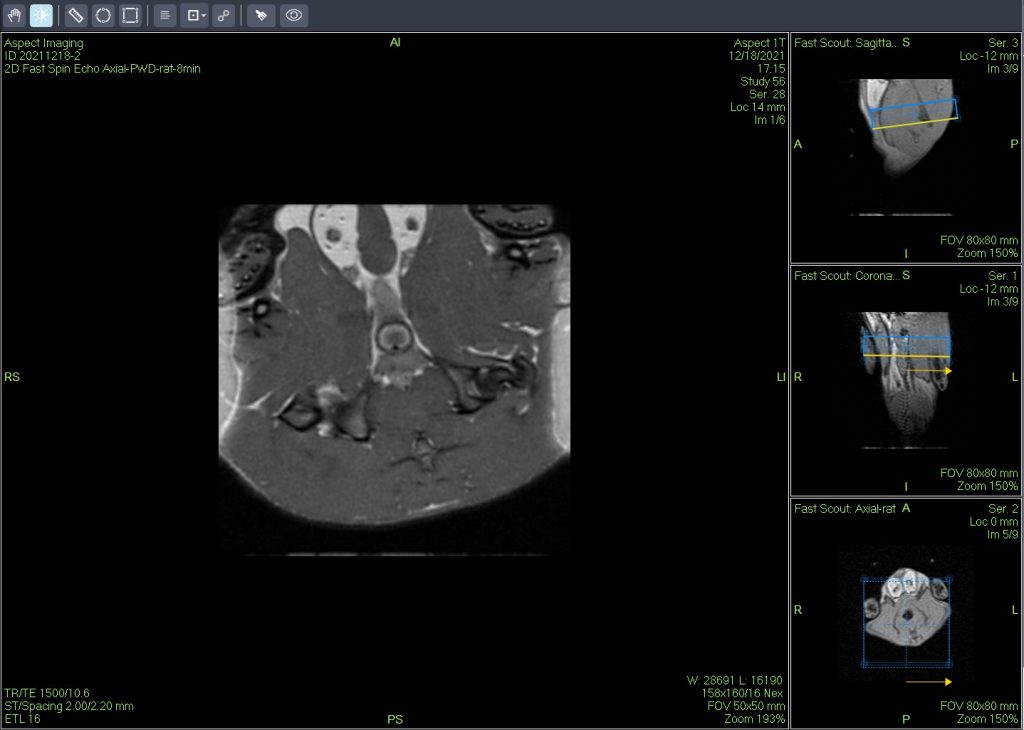

一个新的紧凑型高性能小动物磁共振成像平台(M3),该系统使用一种新的磁铁设计和一套相关的软件,降低了小动物磁共振成像仪的成本和复杂性。

小鼠皮下肿瘤MRI造影成像效果与造影剂代谢过程研究。

使用仪器: 小动物核磁共振成像仪NM20-060H-I 其他相关应用: 核磁共振造影剂弛豫率分析造影剂分析案例 核磁共振成像与分析技术在生命科学领域应用解决方案